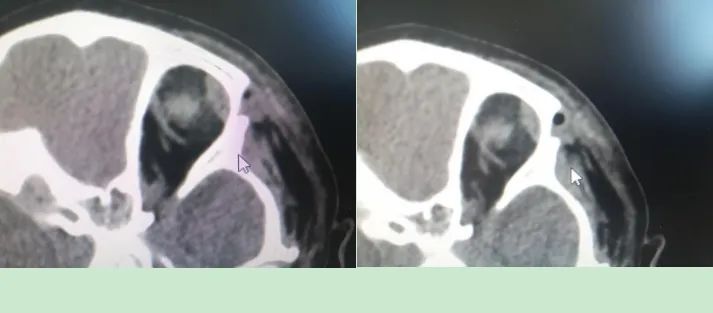

患儿经检查诊断为“左眼眶外侧肿物,性质待查”。眼部CT显示肿物已压迫颅骨,导致颅骨内凹变形,如不及时手术,可能会伤及脑组织。由于CT不能很好反映肿物侵及骨壁情况,同时患儿无法进行核磁扫描,导致肿物的性质及范围不能明确,加之眼球及眼眶内部结构复杂,这都无疑增加了手术的难度和风险。眼科全体医护人员迎难而上,不辜负救死扶伤的神圣使命,经与患儿父母进行多次交流沟通后签署了手术同意书,决定行肿物切除术,手术在全身麻醉下进行,由刘志英主任主刀,卞茹副主任医师、杨月琳医师共同协作完成。由于肿物较大,为术后恢复不影响美观,切口要尽可能小,所以手术全程精细操作,如同在葡萄皮上雕花,经过一个半小时的努力,成功将肿物完整切除,病理结果显示为良性肿瘤。患儿病情恢复良好,顺利出院。该手术的成功也推动我院眼科在眼眶病领域的诊断和治疗更向前迈进。

术中图,可见骨质深坑

术中图,肿物完整切除